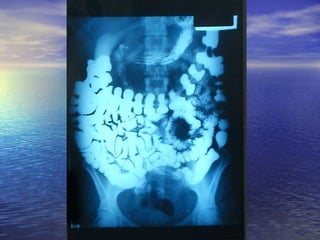

• Estudio radiológico consiste enEstudio radiológico consiste en

administración de 250ml oral de bario y laadministración de 250ml oral de bario y la

obtención de radiografías seriadas delobtención de radiografías seriadas del

intestino, realizadas a intervalos, hastaintestino, realizadas a intervalos, hasta

que el contraste llega al cielo.que el contraste llega al cielo.